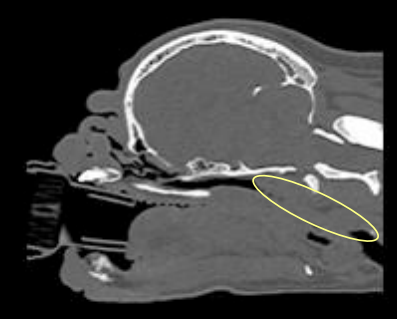

- CT를 찍으면 turbinate 이상과, 작은 naso&oropharynx 공간 보임.

* 엑스레이로는 nasopharynx 정도까지만 확인 가능. 비갑개와 비강 내부 정확하게 확인하려면 CT 필요.